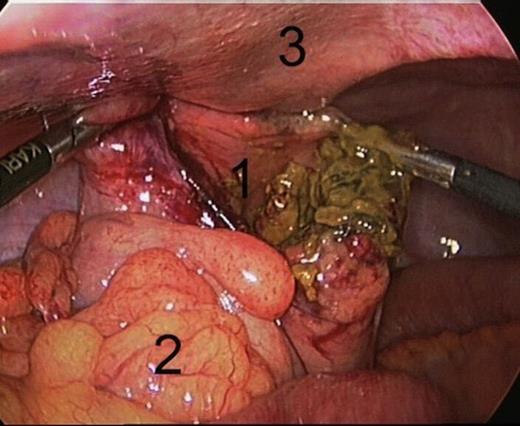

Under general anesthesia patient underwent a laparoscopy in which a defect of the sigmoid was found with only minimal signs of local peritonitis. The defect had a diameter of 9 centimeters and was located approximately 20 cm above the transverse rectal fold (figure 2). Because of the absence of general fecal peritonitis we opted to suture the perforation in two layers with a Vicryl 2.0, without formation of a protective ileostomy. Patient made an uneventful recovery and was discharged in 5 days.

Laparoscopy: defect of the sigmoid:1. Large defect of the Sigmoid, 2. Sigmoid mesocolon, 3. Abdominal wall